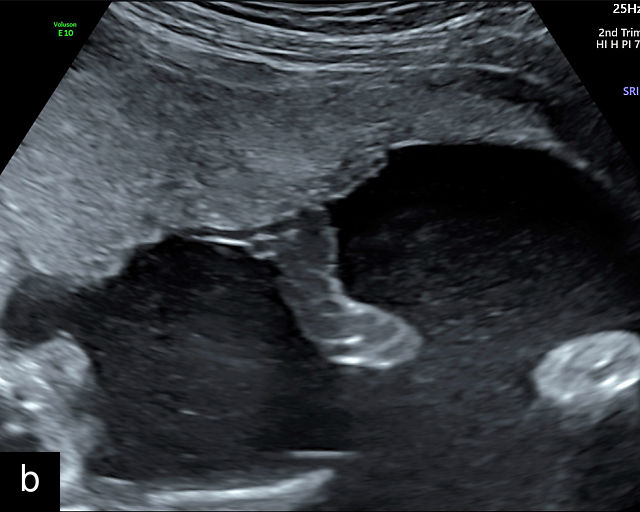

- The umbilical cord insertion (Figure 2b,c) and placental margin (Figure 2d) – Special attention should be paid to the site at which the umbilical cord or vessels insert into the placenta, as well as the marginal regions of the placenta, to identify potential abnormalities.

(a) Transabdominal grayscale ultrasound image of the placenta showing the four key placental regions: the myometrium (gray area), decidua (black line), chorion (light gray thin line), placental body (p), and the chorion–amnion interface. (b) Grayscale ultrasound image of the umbilical cord insertion into the placenta. (c) Same view as in (b) but with color Doppler applied. (d) Normal placental edge (arrow), which is a common location for placental lakes. (e) Rolled placental edges (arrows) in circumvallate placenta (p).